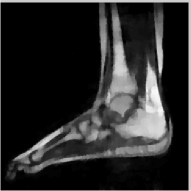

The reconstructions of an ankle image from its 4 fold Cartesian undersampled Fourier data, corrupted with zero mean complex Gaussian noise with a standard deviation σ=10𝜎10\sigma=10, are shown in Fig. 5. This is a really challenging case since the 1-D downsampling pattern is considerably less efficient than the 2-D random pattern used in the previous experiment. We observe that the non-local algorithm provides better reconstructions than the other schemes. Specifically, the TV scheme results in patchy artifacts. The DLMRI scheme results in blurring and loss of details close to the heel. The details are relatively better preserved close to the finger since there are no structures above or below it that aliases to it. By contrast to the classical algorithms, the degradation in performance of the non-local algorithm is comparatively small. The quantitative comparisons of the algorithms on this setting using different images are shown in the top section of Table IV.

Figure 5: Comparison of the algorithms in the presence of noise. We consider the recovery of a 256×256256256256\times 256 MRI ankle image from its Cartesian Fourier sampling pattern (shown in (e)), contaminated by zero mean complex Gaussian noise with standard deviation σ=10𝜎10\sigma=10. The top row shows the original and reconstructed images, while the error images scale by a factor of five are shown in the bottom row. This is a challenging case due to the high 1-D undersampling factors and noise. We observe that the NLS scheme provides the best reconstructions with minimal alias artifacts.